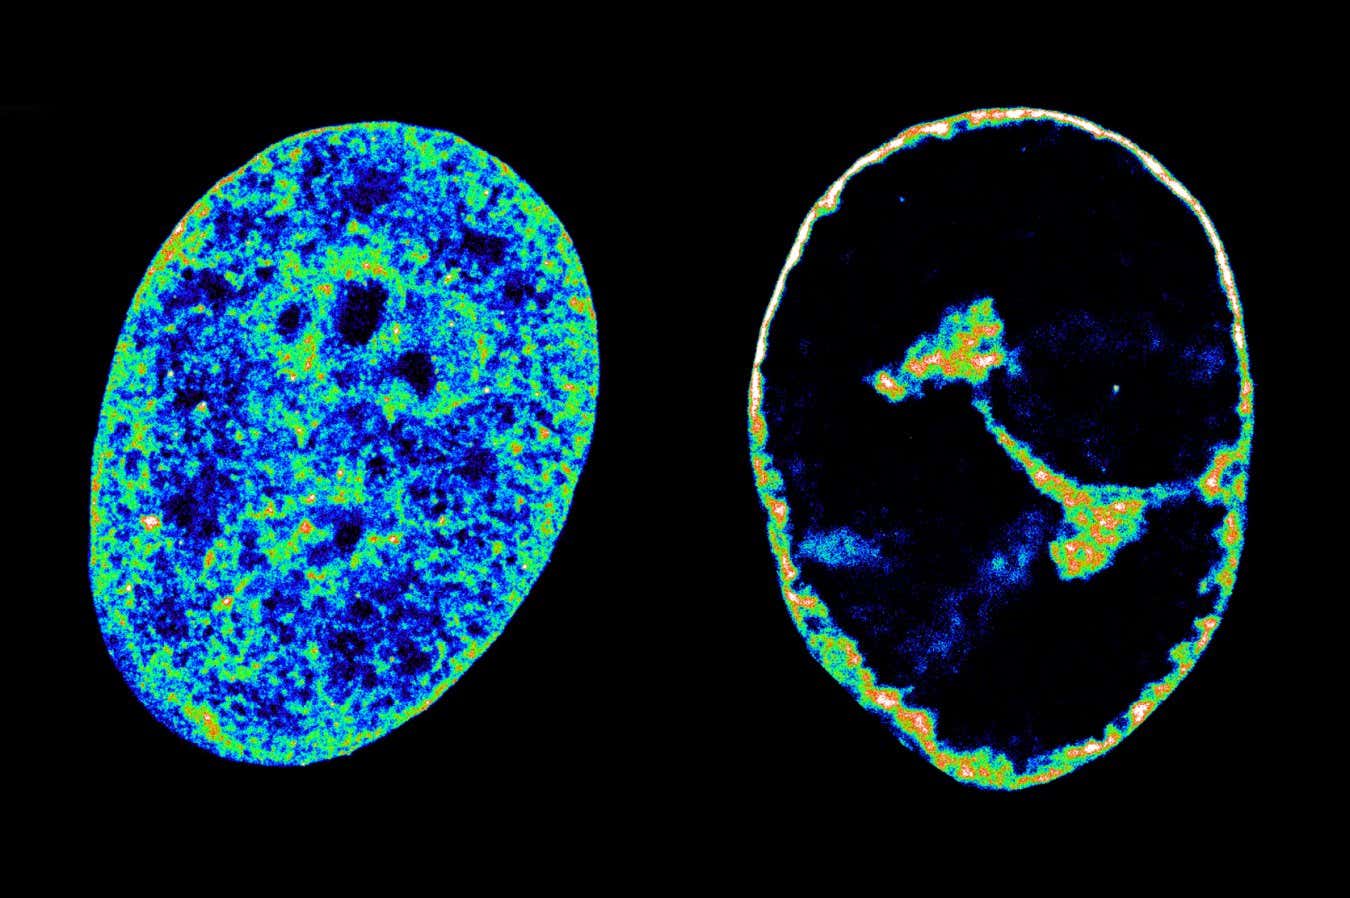

İnsan DNA, hücreler içindeki doğal durumunda (solda), soğuk boğaz virüsü ile enfekte olduktan 8 saat sonra durumu ile karşılaştırıldığında (sağda)

Konakçı hücreleri istila ettikten sonra, virüs, genetik materyalin DNA telleri olarak saklandığı çekirdekte kopyalanır. Bu ipler proteinlerin etrafına sarılır, bazı bölgeler sıkı bobinler oluşturur, içlerindeki genleri inaktive ederken, diğerleri genlerin aktif olduğu daha geniş döngüler oluşturur. Bu daha gevşek bölgelerde, proteinler DNA’yı molekül RNA’ya gevşetebilir ve transkripte edebilir, bu da hücreyi çalışır durumda tutan proteinleri kodlar.

Önceki çalışmalar, HSV-1 enfeksiyonu sırasında insan genomunun hücre fonksiyonunu bozabilecek daha sıkı sarıldığını göstermiştir, ancak bu sarının neden meydana geldiği belirsizdi.

Ancak, bu hırsızlığın konak DNA’nın daha sıkı bobin olmasına neden olan şey olduğunu göstererek, enfeksiyon öncesi hacminin enfeksiyondan sonraki 8 saat içinde büzülmesini sağladı.